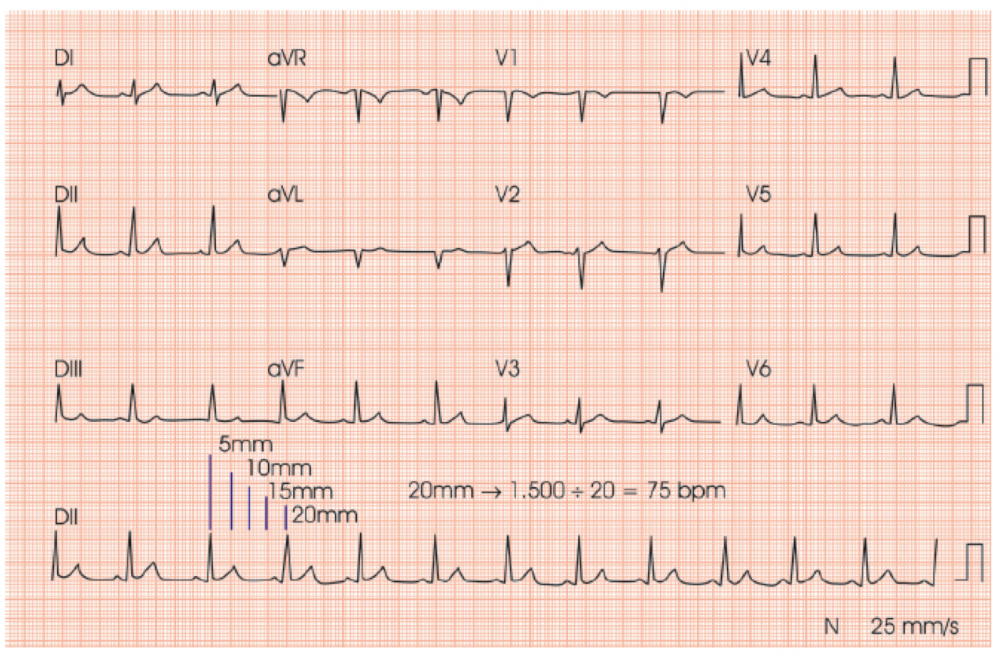

No ECG, o DII longo nos mostra um registro que equivale a 10 segundos, e você pode ver se a distância entre os R-R são sempre iguais ou diferentes. Caso diferentes, estamos diante de uma arritmia cardíaca. Avaliar a Frequência Cardíaca (FC) em uma arritmia pode ser um pouco mais complicado, mas como sabemos que o DII longo nos mostra a quantidade de batimentos em 10 segundos, basta contar o número de complexos QRS e multiplicar por 6 para termos a FC por minuto.

Faixa de ritmo normal na derivação II. O intervalo PR é de 0,15s e a duração do QRS é de 0,08s. Fonte: UpToDate